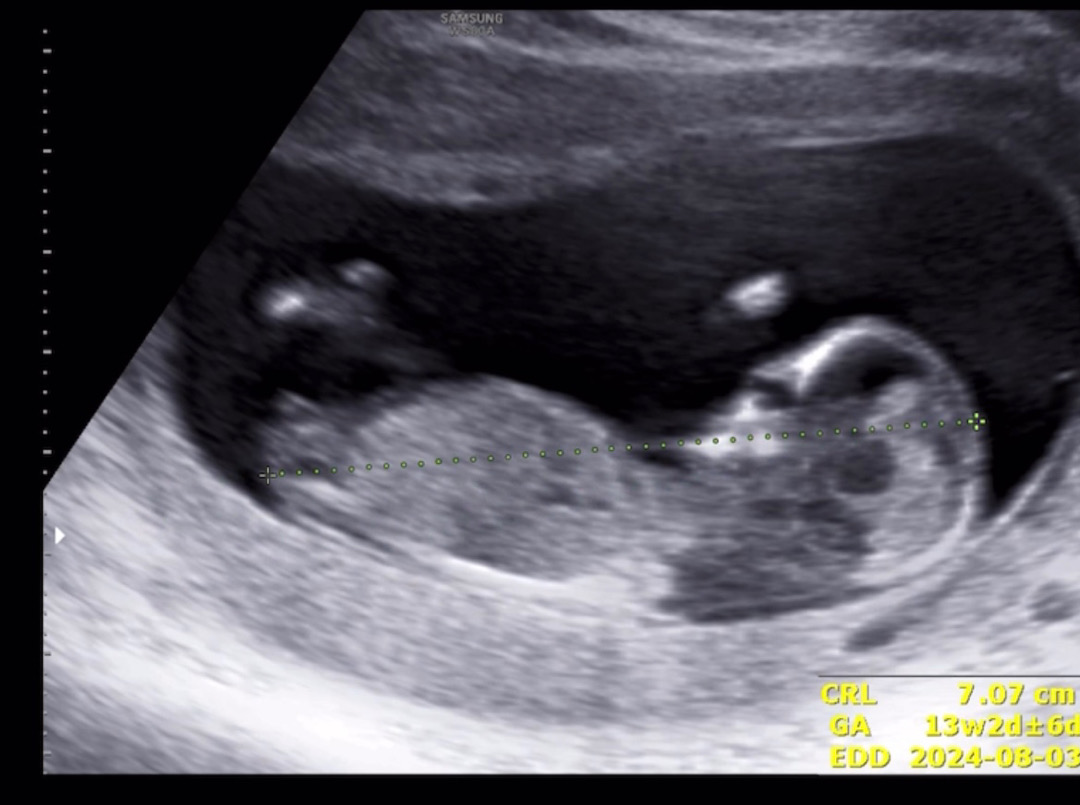

12주 각도법 한번 봐주세요~

주차로는 12주이고 1주정도 더 크다고 하네요! 각도법 예측 부탁드려요!!

딸이용